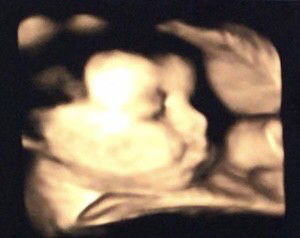

33 week pregnant

Adil ya pembagiannya idung mirip si bapak, bibir ableh seksinya mirip mamah 😂 Ah jadi gk sabar pengen cepet ketemu 🥰🥰 #firstbaby